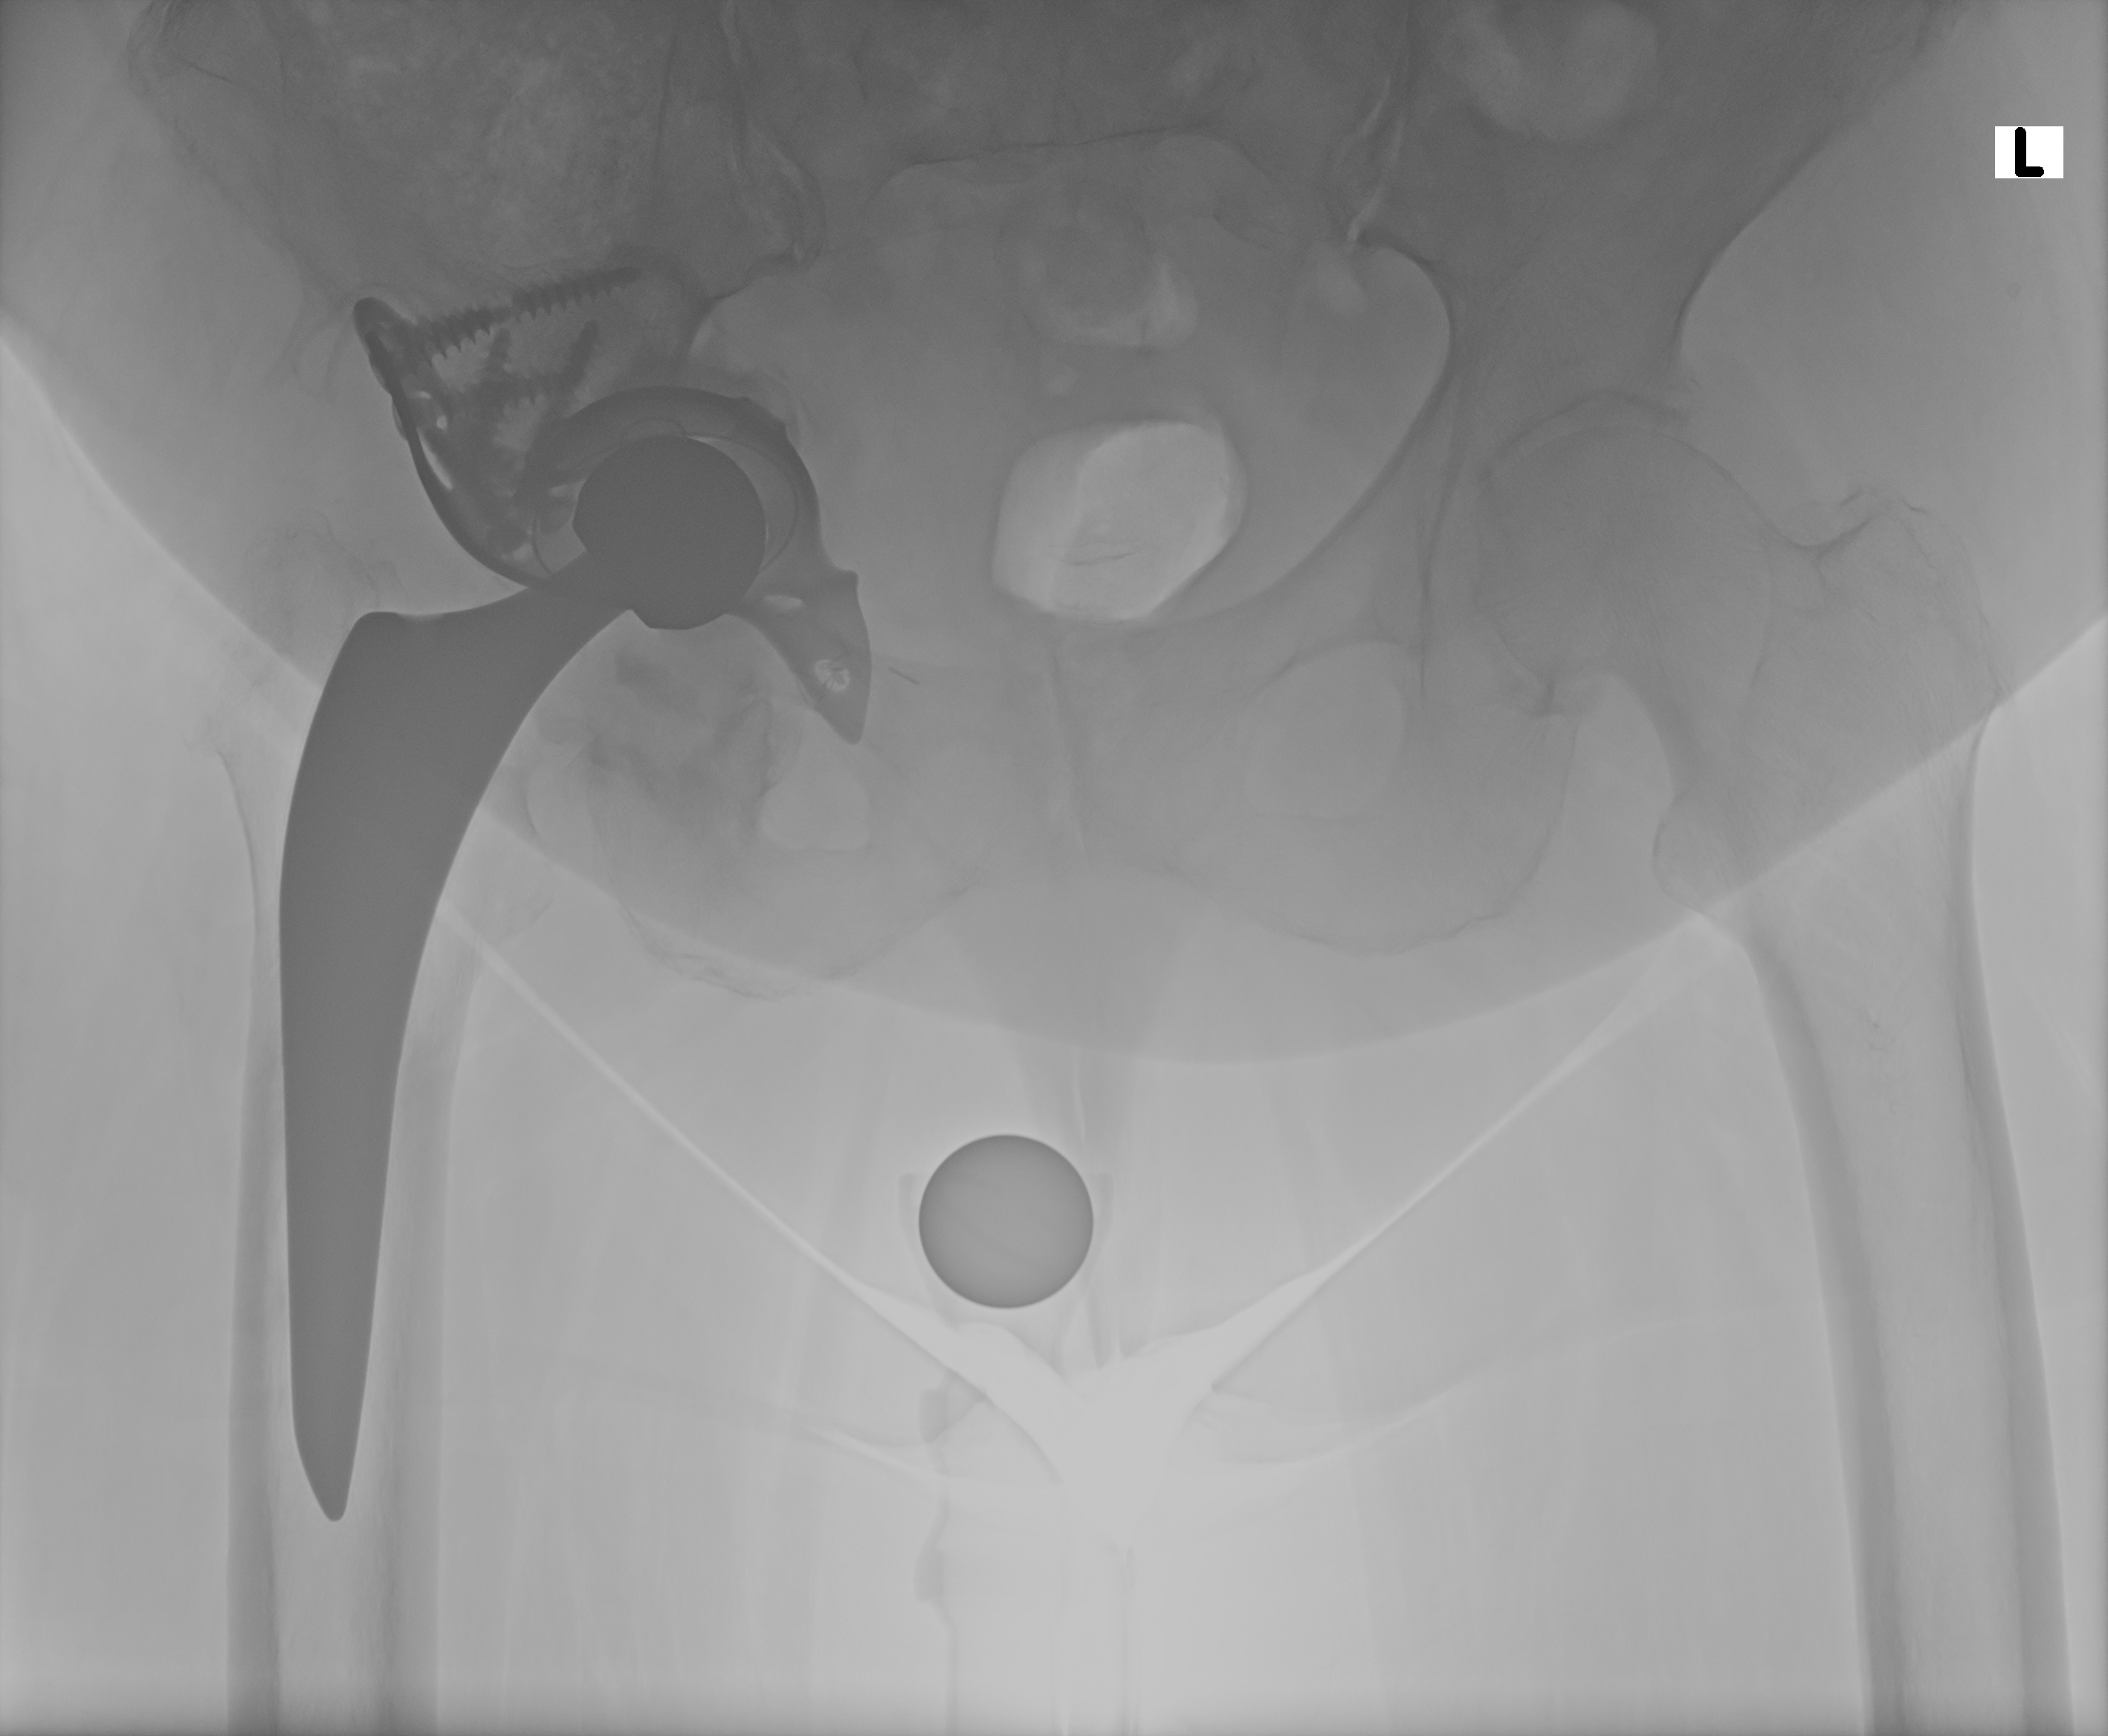

21.11.2025

Röntgen Becken + Hüfte rechts

2 Aufnahmen | 2836x2336 px | 4.3 MB

November 2025

Aktuelle Röntgenbilder + Labor

Röntgen Becken und Hüfte rechts mit Radiologiebefunden, Laborbefund und Arztbericht

Röntgen Becken

DICOM

Luxation der Hüft-TEP

Röntgen Hüfte rechts